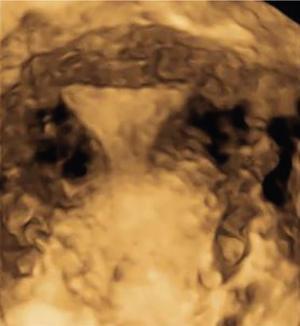

MÜLLERIAN DUCT ANOMALIES Rajani Gorantla Müllerian ducts are a pair of tubular structures that give rise to uterus, cervix, fallopian tubes and upper two-thirds of vagina. Disruption or failure of normal development can result in occurrence of Müllerian duct anomalies (MDAs). These are commonly associated with other congenital anomalies of urinary tract and ovaries due to the close relationship between the development of mesonephric and paramesonephric ducts; few patients also have associated skeletal system anomalies. The prevalence of MDAs in an unselected population was 5.5%; 8% among the infertile women, 12.3% in women with a history of recurrent pregnancy loss and 24.5% in women with miscarriage and infertility. Most of the patients with MDAs are asymptomatic and found incidentally on imaging for any other gynaecological problems, in evaluation of a patient with renal, skeletal or abdominal wall abnormalities. In symptomatic women, complains are related to the type, severity, obstructive anomaly or nonobstructive anomaly. The symptoms can be obstetric or gynaecological related, includes recurrent spontaneous abortions, infertility, preterm labour, intrauterine growth restriction and abnormal foetal lie. Few adolescent girls may present with primary amenorrhoea, hypomenorrhoea, abnormal vaginal bleeding, cyclical pain and mass. Rarely they can present with pelvic inflammatory disease with abnormal vaginal discharge, dyspareunia and urinary tract infections. The female reproductive system develops from a pair of Müllerian or paramesonephric ducts, urogenital sinus and vaginal plate. The ovaries develop separately from the primordial ridge. It is of great importance to understand the normal stages of development, as failure or interruption of any of these stages can lead to a simple to complex spectrum of anomalies. The three stages of Müllerian duct development include: At 6–10 weeks of gestation age, two paired Müllerian ducts and Wolffian ducts formation occurs. When Y chromosome factor (testicular determining factor) is absent, the Wolffian ducts undergo degeneration. The Müllerian ducts further elongate caudally and cross the Wolffian ducts to fuse in the midline. At 10–13 weeks of gestation age, caudal and lateral fusion of the two Müllerian ducts forms primitive uterovaginal canal, which is possessed of solid tissue initially located side by side and further internal canalization leads to the formation of two channels/canals divided by a septum. At this stage, there is reabsorption of the caudal septum and forms single cervical canal and vagina lumen. In around 15–20 weeks of gestation age, complete resorption of the septum takes place in a caudocranial direction from the isthmus to fundus and development of single endometrial cavity results. The fused caudal part of Müllerian ducts gives rise to the uterus, cervix and upper two-thirds of vagina; the unfused cranial part forms the fallopian tubes (Fig. 11.14.1.1). The lower vagina develops from the urogenital sinus, which is separated from the rectum by urorectal septum around 7 weeks of gestation age. The primitive uterovaginal canal embeds into the dorsal wall of urogenital sinus and forms Muller’s tubercle. Around 13 weeks of gestation, two solid masses known as sinovaginal bulbs originate from the upper part of the Muller’s tubercle, further proliferate into the caudal end of the uterovaginal canal to become a solid vaginal plate. Later canalization or degeneration of the central cells of the vaginal plate forms the lower vagina, which is usually completed by 20 weeks’ gestation. The vertical fusion of the upper and lower vagina occurs with resorption of tissue in between and forms single vaginal cavity (Fig. 11.14.1.2). The vaginal lumen is separated from the urogenital sinus by the hymenal membrane. Just before birth, the hymen normally ruptures due to retrogression of the central epithelial cells. However, a thin fold of mucous membrane persists around the vaginal introitus. The ovaries develop separately from migration of primordial germ cells to the genital ridge. Ureteric buds develop separately and concurrently. So renal anomalies are most commonly associated with MDAs with an association of 30%–50%. Various classification systems have been proposed over the past several decades to describe MDAs. Ideally, same classification system needs to be followed by a gynaecologist, surgeon and radiologist for better communication. Buttram and Gibbons classification was suggested in 1979, and it was based upon the level of failure in normal development and segregate the anomalies into groups with similar clinical manifestations, treatment, and prognosis for foetal salvage. According to Buttram and Gibbons, the uterine anomalies were classified into six classes as described in Table 11.14.1.1. The drawback is the lack of classification of vaginal and other anomalies separately. The ASRM (previously the American Fertility Society – AFS) classification system is the most widely accepted classification worldwide over the past years and was introduced in 1988. According to this classification, MDAs are classified into seven classes (class I to class VII) as mentioned in Table 11.14.1.2. However, several limitations have been described by Grimbizis and Campo in 2010 (Fig. 11.14.1.3). The drawbacks of the ASRM classification system are as follows: Hence in 2016, an updated classification of uterine septum, that is ASRM-2016 was proposed and officially approved morphometric criteria are given for distinguishing between septate, normal/arcuate and bicornuate uteri (Table 11.14.1.3). The VCUAM classification was proposed in the year 2005. The main concern is to provide a simple, systematic, clinical classification in addition to providing a precise reflection of the entire malformation. The female genital organs were divided into the following subgroups in accordance with the anatomy: vagina (V), cervix (C), uterus (U) and adnexa (A). Associated malformations were assigned to a subgroup (M) relative to each specific organ. The disadvantage is due to its inherent complexity, and more than 56,700 individual combinations of anomalies are possible. ESHRE and ESGE established a common working group named CONgenital UTerine Anomalies (CONUTA) in order to devise an improved classification system (Table 11.14.1.4). It was published in 2013. Anatomy is the basis for systemic categorization of the MDAs. The subclasses are divided by the different degrees of uterine deformity and their clinical significance (Fig. 11.14.1.4). Cervical and vaginal anomalies are classified into independent supplementary subclasses (Figs. 11.14.1.5–11.14.1.6). For most of the clinicians, it helped as starting point for the development of guidelines for their diagnosis and treatment. The malformations are graded according to severity, U0–U5, C0–C4 and V0–V4, with U5, C4 and V4 being more severe. Class U3 incorporates bicorporeal fusion defects (didelphys and bicornuate) as this was considered as a more functional mode of classification. Arcuate uterus was not included separately, but this is categorized under normal variant into class U1c. Recent studies have demonstrated that the ESHRE/ESGE system provides an effective and comprehensive classification for almost all the currently known MDAs and overcomes the limits of previous classifications. However, there is a relative overdiagnosis of septate uterus with the application of ESHRE–ESGE criteria has been reported and which potentially might lead to unnecessary surgical overtreatment. C0 C1 C2 Normal cervix Septate cervix Double ‘normal’ cervix C3 C4 Unilateral cervical aplasia Cervical aplasia U4 V0 V1 V2 V3 Normal vagina Longitudinal nonobstructing vaginal septum Longitudinal obstructing vaginal septum Transverse vaginal septum and/or imperforate hymen V4 Vaginal aplasia C MDAs’ characterization and classification is of great significance, as the treatment is determined by the type and severity of abnormality. The various imaging modalities available include: HSG was the most recognized imaging modality, earlier to the development of the ultrasonography (USG) and MRI. It is an invasive fluoroscopic-guided procedure for uterine and tubal assessment, and is performed during the midproliferative phase of the cycle, ideally between days 7 and 10 of the cycle when endometrium is thin. Fluoroscopic spot images obtained to evaluate uterine configuration, uterine filling defects and fallopian tube patency. HSG allows evaluation of only the component of the uterine cavity that communicates with the cervix. The anatomic information about myometrium and external fundal contour will not be provided by HSG. The diagnostic criteria used to diagnose MDAs on HSG include: HSG findings of different MDAs are described in Table 11.14.1.5 and Fig. 11.14.1.10. Virtual HSG is a noninvasive technique performed by using a computed tomography (CT) scanner, done 45 s after the contrast material instillation begins. Contraindications are similar to those for HSG and include pregnancy and active pelvic infection. There is no necessity for retraction of the uterus or manipulation of the cervix. The procedure is quick, easy and prophylactic administration of antibiotics is not required. The use of a power injector helps to ensure a steady low pressure of instillation. The procedure is less painful, more comfortable and easily tolerated by patients than conventional HSG. Radiation exposure sometimes requires cervical clamping, which may result in complications such as bleeding and infection. Transabdominal pelvic ultrasound can diagnose uterine anomalies with accuracy rate of 47%. Two-dimensional transvaginal ultrasound (TVUS) has high sensitivity and specificity than transabdominal study and provided some information about external and internal fundal contours. The detection rate is high if the scan is performed in secretory phase due to better visualization of endometrium. Three-dimensional USG shows great accuracy than 2D USG in evaluation of the uterine morphology. The technique of 3D USG varies with different vendors. It displays both the external and internal fundal contours and lower uterine segment by acquisition of single coronal view of uterus (c-view) (Fig. 11.14.1.11). The only disadvantage is that it is transvaginal study and shall not be done in paediatric age group and sexually inactive women. Three-dimensional TVUS has become the first line of screening tool in most of the infertility clinics as it is noninvasive, faster, repeatable, allows storage of volume data and has multiplanar capability for systematic evaluation of the uterine and cervical cavities. The salient features of various Müllerian anomalies on 3D USG are described in Table 11.14.1.6 with images. Three-dimensional ultrasound is combined with sonosalpingography in this technique and provides better delineation of the uterine morphology. It is a less invasive procedure done in proliferative phase with instillation of saline into the uterine cavity and assessment of the uterus will be done. MRI is a universally accepted imaging modality in the documentation of MDAs and accuracy rate of 100% have been reported. MRI provides excellent delineation of both the internal and external uterine anatomies. T2-weighted (T2W) images are the mainstay of pelvic imaging and are performed without fat suppression. T1-weighted (T1W) images are mainly for the haemorrhagic content. The disadvantages of MRI include time-consuming procedure, not cost-effective, large body habitus, pacemakers, recent surgical history and claustrophobia. The current and proposed MRI protocol given by the European Society of Urology (ESUR-MRI protocol) intends a dedicated evaluation of MDAs as mentioned below (Fig. 11.14.1.12): Vaginal anomalies can be accurately diagnosed with the prior administration of the ultrasound gel, to distend vagina (Fig. 11.14.1.13). It will help in better diagnosis of complex vaginal anomalies, like vaginal septations or vaginal duplication. The normal MRI appearance of uterocervical canal and vagina are shown in Fig. 11.14.1.14. Uterine aplasia/hypoplasia/agenesis is class 1 MDA according to ASRM classification and U5 uterine anomaly according to ESHRE classification. It is a formation defect of the paramesonephric ducts with complete or segmental agenesis of uterus and vagina. The incidence rate is around 10%–15% of all MDAs and considered as the most severe form of uterine anomaly. Most of them have complete uterovaginal agenesis with no single completely developed uterine cavity and are associated with Mayer–Rokitansky–Küster–Hauser syndrome (MRKHS). Two types of this syndrome are depicted. The typical form or type A represents the absence or remnants of the uterus, cervix, upper two-thirds of vagina with normal ovaries and fallopian tube (Fig. 11.14.1.15). The atypical form or type B is associated with the abnormalities of the ovaries, fallopian tubes and genitourinary system (Fig. 11.14.1.16). In a few cases (approximately 10%), unilateral or bilateral uterine remnants and with or without endometrial cavity will be seen (Fig. 11.14.1.17). Most of them present with primary amenorrhoea due to complete uterovaginal agenesis and manifest as MRKHS. These patients have normal secondary sexual characteristics due to the preserved normal ovarian function and phenotype. If uterine remnants with functional cavity is present, will present with cyclical pain along with amenorrhoea due to cryptomenorrhoea and haematometra. USG is the first modality for identification of these anomalies, absence of uterus with normal ovaries is diagnostic. But, it is difficult to locate the uterine remnants and cavity due to small acoustic window. MRI is the gold standard and it classifies into uterovaginal agenesis and hypoplasia. If hypoplasia is identified, sagittal and axial sections are taken. These remnants are seen as T2 hypointense tubular structures, located in close relation to ovaries in the adnexa. Once we identify the uterine remnants, it is important to look for the functional endometrial cavity. These will have reduced endometrial and myometrial width. MRI can easily delineate the zonal anatomy due to its high soft tissue contrast resolution. The management of Müllerian agenesis consists of counselling for the patient and her parents. Some patients with MRKHS opt for creation of neovagina for normal sexual life. Various techniques are available. In the presence of a functional Müllerian remnant, regardless of whether it is communicating or not, medical suppression of menses can be initiated and should be followed by laparoscopic removal of the hypoplastic remnant. Unicornuate uterus or hemiuterus is defined as the unilateral uterine development and the contralateral Müllerian duct could be either partially formed or absent. It is a formation defect and the necessity to classify it in a different class than that of uterine agenesis, which is also a formation defect, is due to the existence of a fully developed functional uterine hemicavity. It is considered as class II anomaly according to ASRM classification and class U4 according to ESHRE classification. The frequency rate is around 20% of MDAs. Renal anomalies most often occur in association with unicornuate uterus and usually on the same side of uterine agenesis. Further unicornuate uterus is divided into two subclasses depending on the presence or absence of a functional rudimentary cavity in ESHRE classification: In ASRM classification, unicornuate uterus is divided into four subcategories: Mostly asymptomatic and presence of the noncommunicating uterine remnants will be identified at the time of infertility work up or caesarean section. If a functional cavity is present, the presentation is dysmenorrhoea or haematometra in an adolescent. The common obstetrics-related complications include abnormal foetal lie, intrauterine growth retardation, preterm delivery, placental abnormalities and uterine rupture. Gynaecological complications are ectopic pregnancy and endometriosis due to retrograde menstruation. On imaging, unicornuate uterus is seen as tubular and fusiform or banana-shaped structure at paramedian location, the endometrium is narrow and tapers to the apex with normal myometrial anatomy and reduced uterine volume. The rudimentary cavity or remnants are better depicted on 3D USG (Fig. 11.14.1.18) and MRI. However, MRI is superior to USG due to its high soft tissue resolution. The rudimentary cavity can communicate with main cavity or connected by fibrous band. The nonfunctioning cavity will be seen as T2 hypointense structure with loss of zonal anatomy (Figs 11.14.1.19 and 11.14.1.20), whereas the functioning cavity will show the deformed zonal anatomy (Fig. 11.14.1.21), and its complications like haematometra as T1/T2 hyperintense endometrial collection. Unicornuate uterus without rudimentary cavity does not require any procedure. But in the presence of communicating or noncommunicating rudimentary horn, surgical resection must be considered to prevent complications. Uterine didelphys is a class III MDA based on the ASRM classification and class U3b bicorporeal uterus according to ESHRE classification with an incidence rate of 5% among the uterine anomalies. It is a lateral fusion defect; results from complete failure of the Müllerian duct fusion. Two noncommunicating endometrial cavities with preserved zonal anatomy are seen with separate cervix. According to ESHRE classification, it is defined as external fundal indentation completely dividing the uterine corpus up to the level of external cervical os. It is most commonly associated with longitudinal vaginal septum in around 75% of cases. Some patients may show transverse vaginal septum and these will be obstructive or nonobstructive type. Renal anomalies are also commonly associated with uterine didelphys. Uterine didelphys is usually asymptomatic and diagnosed incidentally on pelvic examination or caesarean section. The uterine didelphys with obstructed vagina (Fig. 11.14.1.22) will present at adolescence as dysmenorrhoea, haematometrocolpos and haematosalpinx. Sometimes retrograde menstrual flow can cause endometriosis and pelvic adhesions. Obstetric-related complications include abortion/foetal growth restriction and poor pregnancy outcome. The uterine didelphys with obstructed hemivagina due to transverse vaginal septum and associated ipsilateral renal agenesis are the manifestations of the syndrome called obstructed hemivagina and ipsilateral renal agenesis anomaly/Herlyn–Werner–Wunderlich (HWW) syndrome (Fig. 11.14.1.23).